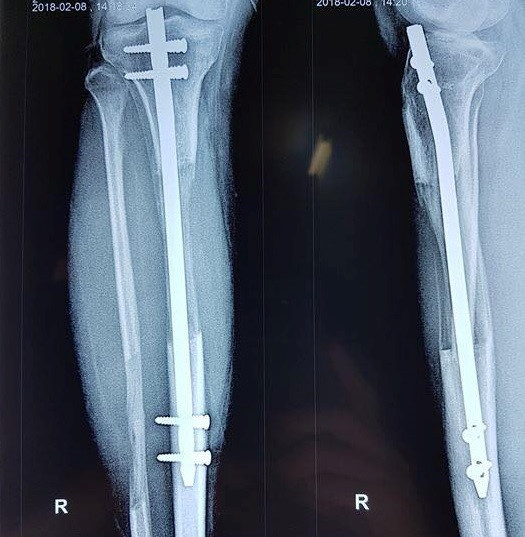

Sau ca mổ để cắt xương, xuyên đinh qua đầu xương và lắp khung bên ngoài để căng dãn, chiều cao của Nam được từ từ kéo dài với tốc độ 1 mm/ngày.

“Sau 70 ngày, Nam đã tăng thêm 7 cm. Chúng tôi vẫn khuyên các bệnh nhân chỉ nên dừng lại ở con số này để hạn chế thấp nhất các biến chứng. Tuy nhiên, khi đạt chiều cao này, bệnh nhân vẫn quyết tâm xin được tiếp tục kéo dài. Khi kiểm tra đủ điều kiện, Nam đã tiếp tục tới 100 ngày mới dừng với chiều cao tăng thêm 10 cm”, PGS Đoàn chia sẻ.

Tháng 2, Nam đã được tháo khung và đinh, có thể đi lại bình thường với sự trợ giúp của nạng. Nam sinh đã quay lại Nhật để tiếp tục việc học chỉ sau 7 tháng.

"Đây là trường hợp cải thiện được chiều cao nhiều nhất (10 cm), cũng là một trong những người nghị lực nhất, chịu khó tập luyện, nên sau khi tháo khung, bắt vít chốt đã đi lại được luôn", PGS Đoàn cho biết thêm.